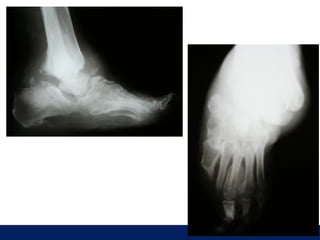

OLGU No 1   İ.K., 57y, E

ÖĞÜT